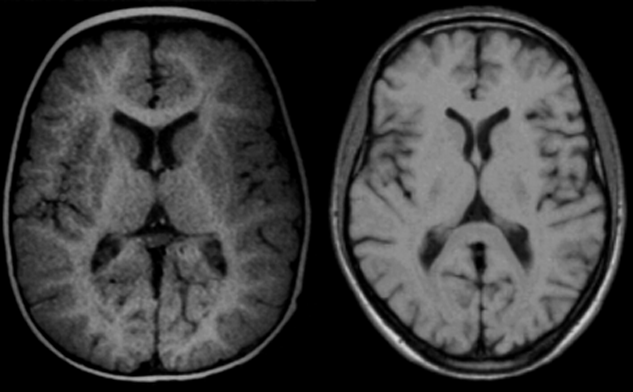

Figura 09-12:

Brain images of (a) an infant of 11 months, and (b) an adult at 0.5 T. The same pulse parameters were used (SE: TR = 500 ms, TE = 20 ms). Windowing is slightly dif­fe­rent.

Still, image contrast, in particular con­trast bet­ween gray and white matter is ob­vi­­ous­ly not the same because in the infant mye­li­na­tion has not reached the adult stage and both T1 and T2 of white matter are higher than T1 and T2 of gray matter.